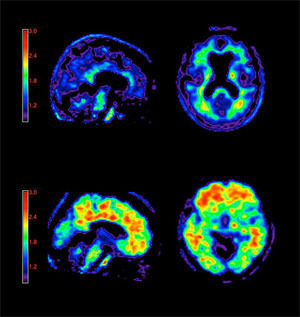

1. Imagen por Resonancia Magnética

1. Tomografía por emisión de positrones

1. Estudio del cerebro vivo